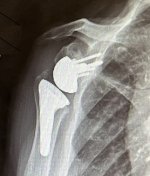

this is what a reverse joint replacement looks like where the ball and socket swap places.

IMG_6798.JPG